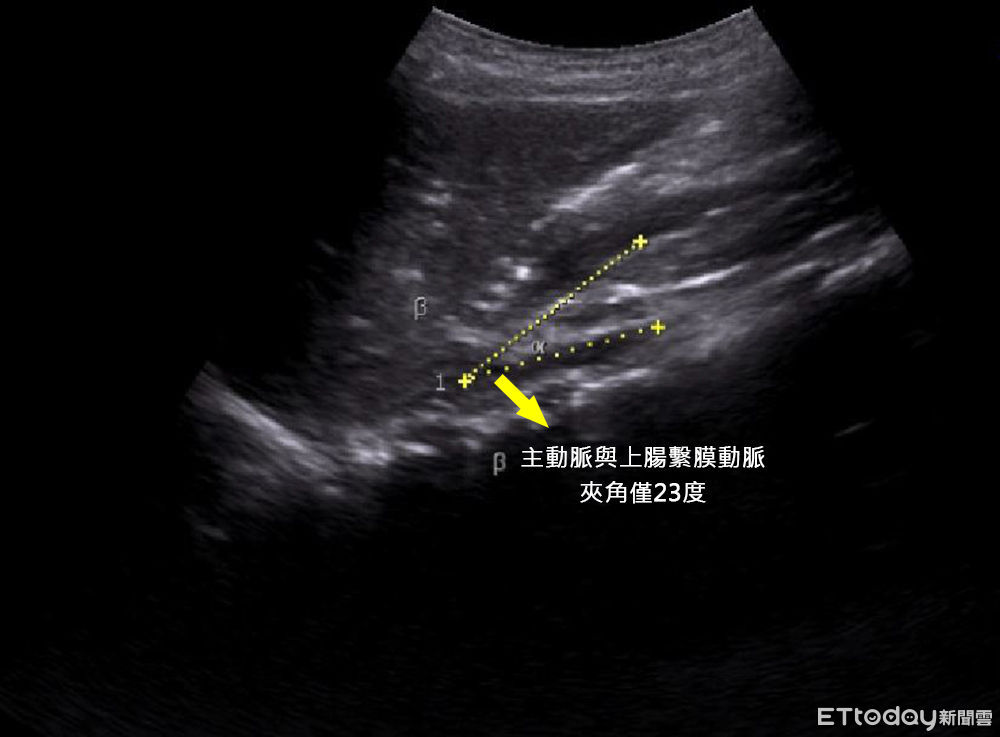

廖子涵表示,經超音波和電腦斷層檢查,發現男孩的主動脈與上腸繫膜動脈之間夾角只有23度,但夾角正常時大約38到65度之間,研判是因為太瘦,導致上腸繫膜動脈缺少脂肪支撐,壓迫到十二指腸,導致食慾不振與頻繁的噁心嘔吐,即「上腸繫膜動脈症候」,解決之道是「增胖」,來增加上腸繫膜動脈支撐的脂肪,讓夾角慢慢的增大,以解除對十二指腸的壓迫。